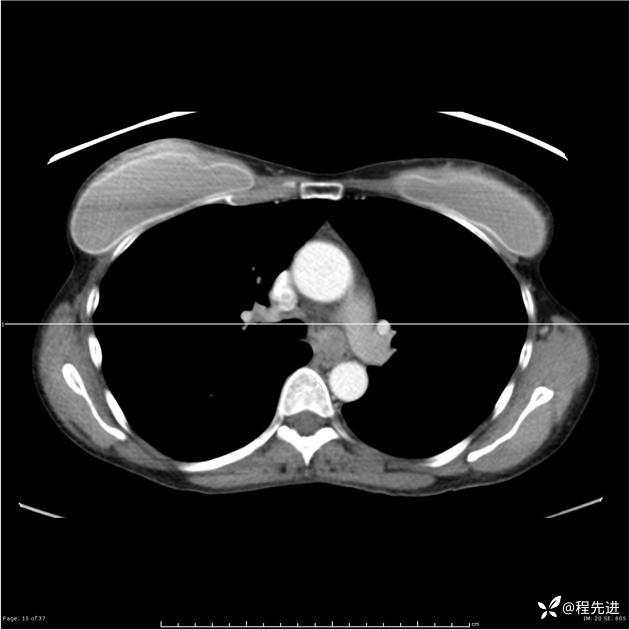

病例女,53岁,气管、左主支气管、下叶支气管内结节,乳头状瘤?期待你的精彩解读

女,53岁

乳头状瘤?